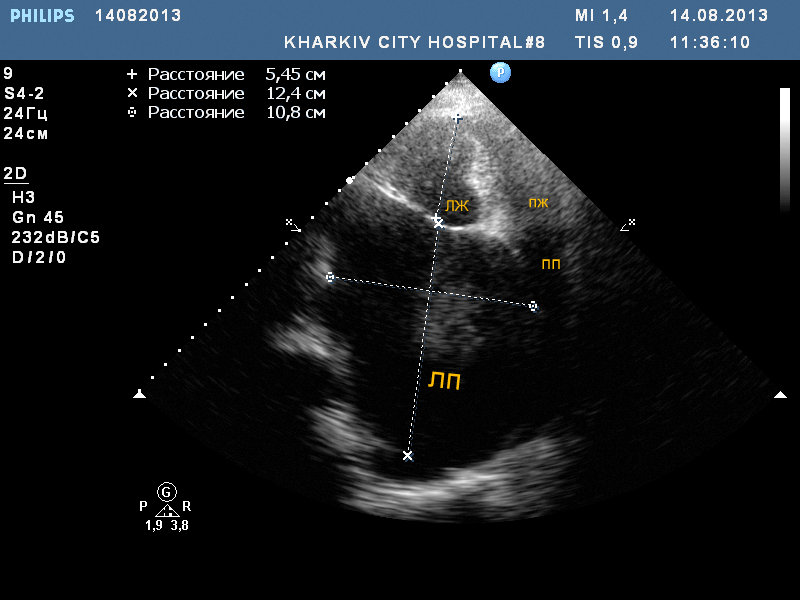

Только что смотрел пациентку 82 года. Не было много времени, потому немного видео и фото. Удивил размер левого предсердия - 10.см.

В полости ЛП визуализируется спонтанное контрастирование тока крови.

Я смотрю в зеркальном отображении (не классически) . Левый желудочек по левую руку, правый по правую. Кстати правое предсердие в 10 см я не видел. А вы что подумали?

Спросил из-за толщины стенки ПЖ и уровня отхождения створок МК и ТК

Уровень отхождения створок стандартный. Просто из-за растянутого ЛП выглядит "необычно". Но и такой размер ЛП тоже "необычный".